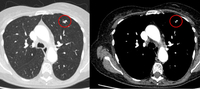

Computed tomography (CT) sections from two cases with benign perifissural nodules. Note the smooth margins and the normal undisturbed adjacent fissure

From the collection of Dr George Tsaknis, MD, PhD, FRCP(London), MRQA, MAcadMEd, PGCert; used with permission